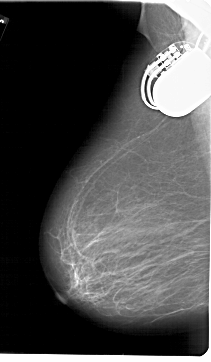

A_1729_1.LEFT_MLO

LEFT_MLO LINES 6871 PIXELS_PER_LINE 4006 BITS_PER_PIXEL 12 RESOLUTION 43.5 NON_OVERLAY